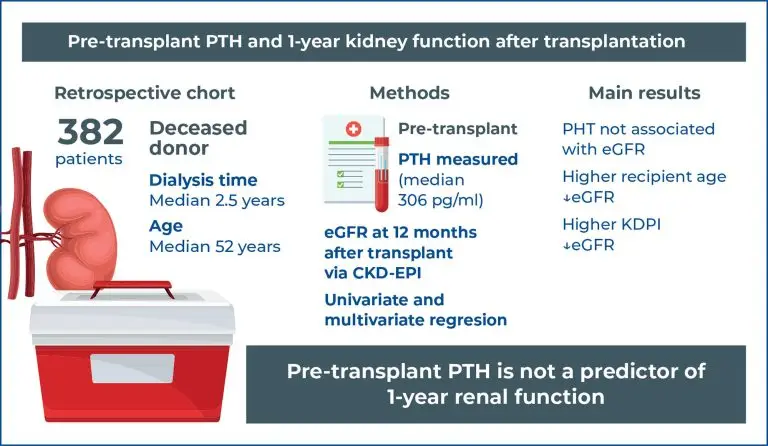

Highlights ■ Pre-transplant parathyroid hormone levels were not linked to kidney function at 1 year post-transplant. ■ Recipient age showed a negative association with renal function at 12 months. ■ The Kidney Donor Profile Index was a strong predictor of graft function. ■ Individualized risk assessment remains essential for kidney transplant prognosis. ABSTRACT Objective: This study aimed to evaluate the association between pre-transplant parathyroid hormone levels and renal function 1-year after kidney transplantation. Methods: This retrospective cohort study was conducted […]

Keywords: Glomerular filtration rate; Kidney transplantation; Parathyroid hormone